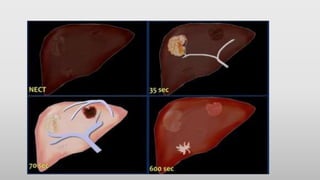

• This figure is to summarize the enhancement patterns.

• In the late arterial phase at 35 sec hypervascular lesions like HCC,

FNH, adenoma and hemangioma will enhance optimally, while the

normal parenchyma shows only minimal enhancement.

• Hypovascular lesions like metastases, cysts and abscesses will not

enhance and are best seen in the hepatic phase at 70 sec p.i.

• Fibrotic lesions like cholangiocarcinoma and fibrotic metastases hold

the contrast much longer than normal parenchyma.

They are best seen in the delayed phase at 600 sec p.i.

This late enhancement is comparable to what is seen in cardiac

infarcts in MRI of the heart.

• This figureis to summarize the enhancement patterns. • In the late arterial phase at 35 sec hypervascular lesions like HCC, FNH, adenoma and hemangioma will enhance optimally, while the normal parenchyma shows only minimal enhancement. • Hypovascular lesions like metastases, cysts and abscesses will not enhance and are best seen in the hepatic phase at 70 sec p.i. • Fibrotic lesions like cholangiocarcinoma and fibrotic metastases hold the contrast much longer than normal parenchyma. They are best seen in the delayed phase at 600 sec p.i. This late enhancement is comparable to what is seen in cardiac infarcts in MRI of the heart.